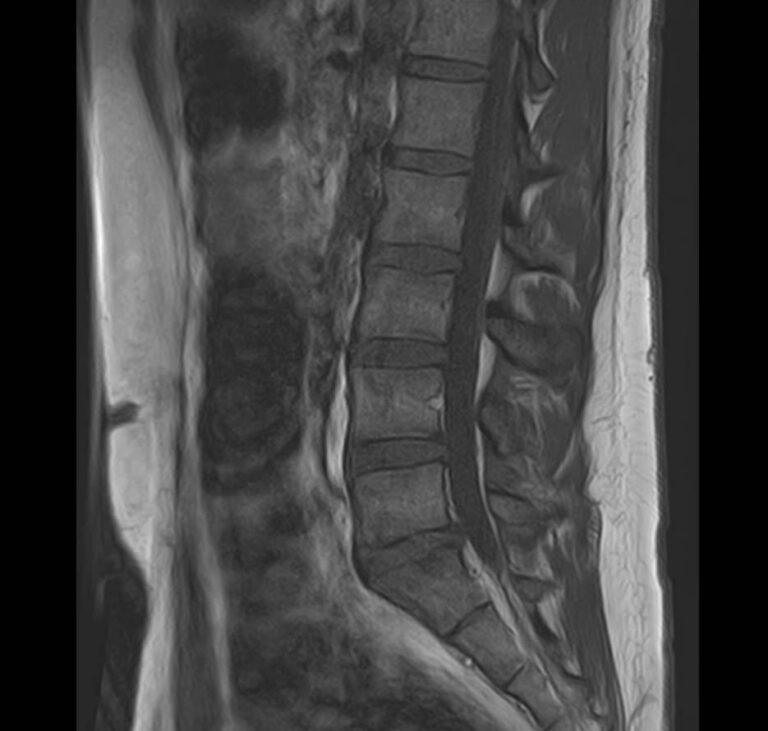

Магнитно-резонансная томография является наиболее чувствительным и эффективным методом диагностики дегенеративно-дистрофических заболеваний, травматических, воспалительных изменений, а также опухолевых процессов позвоночника. Метод позволяет оценить состояние структур позвонков, позвоночного канала с расположенным в нем спинным мозгом и окружающих мягких тканей, кроме того является основным способом диагностики демиелинизирующих заболеваний спинного мозга.

В клинике Доступная медицина установлен новейший высокопольный томограф экспертного класса TOSHIBA VANTAGE TITAN 1,5 Тесла, на котором выполняется комплексное обследование позвоночника. За счет высокой напряженности магнитного поля аппарат при сканировании создает изображения на плоскости превосходной четкости, затем с помощью компьютерных приложений данные преобразуются в изображения трехмерного формата, что обеспечивает точность и достоверность диагностики.

При подозрении на распространенный процесс с поражением различных уровней позвоночника в клинике «Доступная медицина» возможно проведение комплексной МРТ позвоночника – 3 отдела.